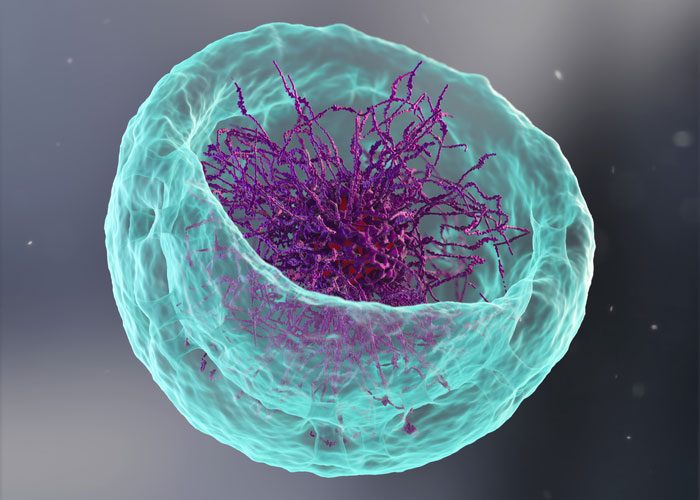

B cell discovery could supercharge future vaccine development

New research reveals how B cells balance mutation and clonal expansion to refine their antibodies. This discovery could lead to more targeted and effective vaccine designs for various diseases.